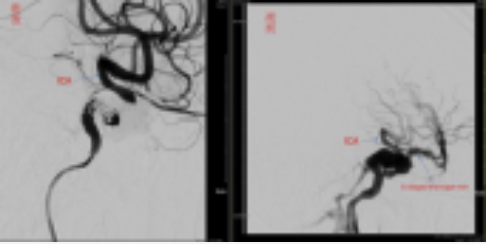

圖上為腦血管簍管栓塞手術

栓塞前頸動脈(ICA)血流經簍管直接流到靜脈竇,甚至倒灌到腦部的靜脈,簍管栓塞後,頸動脈即完整呈現,倒灌的靜脈立刻消失。